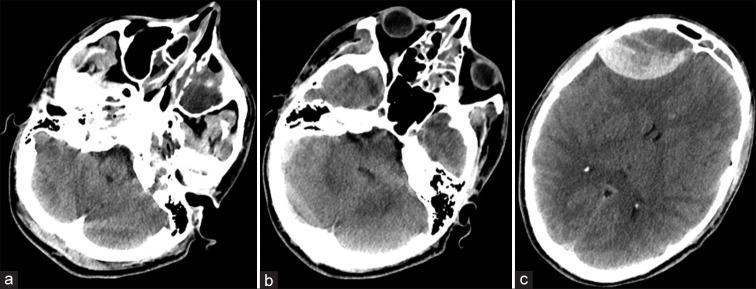

Spontaneous and nontraumatic epidural hematoma (SEDH) is a rare entity. Etiology is various, including vascular malformations of the dura mater, hemorrhagic tumors, and coagulation defects. The association between SEDH and craniofacial infections is rather unusual.

A total of 18 scientific publications, corresponding to 19 patients, met the inclusion criteria for the qualitative and quantitative analysis. Patients were mostly adolescents, with a clear male predominance. SEDHs frequently occurred in the frontal area, usually near the site of the infection. Surgical evacuation was the treatment of choice with good postoperative outcomes. Endoscopy of the involved paranasal sinus should be achieved as soon as possible to remove the cause of the SEDH.

自发性非创伤性硬膜外血肿(SEDH)是一种罕见的病症。病因多种多样,包括硬脑膜血管畸形、出血性肿瘤和凝血缺陷。SEDH与颅面感染之间的关联相当罕见。

共有18篇科学出版物,对应19例患者,符合定性和定量分析的纳入标准。患者大多为青少年,男性明显占主导。SEDH常发生在额叶区域,通常靠近感染部位。手术清除是首选治疗方法,术后效果良好。应尽快对受累鼻窦进行内镜检查以消除SEDH的病因。